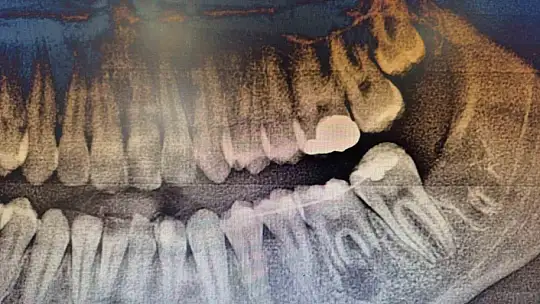

İleri düzey çürük nedeniyle daimi azı dişi çekilen hastaya, yaşı gereği çene gelişimi devam ettiği için klasik implant tedavisi uygun görülmedi. Bunun yerine, hastanın ağzında gömülü halde bulunan yirmi yaş dişi, uzman ekip tarafından cerrahi operasyonla çıkarılarak çekilen dişin yerine nakledildi.

Operasyon sırasında, dişin sağlıklı bir şekilde tutunmasını sağlamak için hastanın kendi kanından elde edilen PRF (Platelet Rich Fibrin) materyali, nakil öncesi hazırlanan diş yuvasına yerleştirildi. Bu uygulama, doku iyileşmesini hızlandıran ve hücre yenilenmesini destekleyen doğal bir yöntem olarak öne çıkıyor. Bu tedavi yöntemi, hastanın kendi dişi kullanıldığı için doğal görünüm, uyum ve fonksiyon açısından büyük avantaj sağlıyor. Aynı zamanda, vücut tarafından kabul edilme oranı yüksek olduğundan, uzun vadeli başarı şansı da oldukça yüksek.